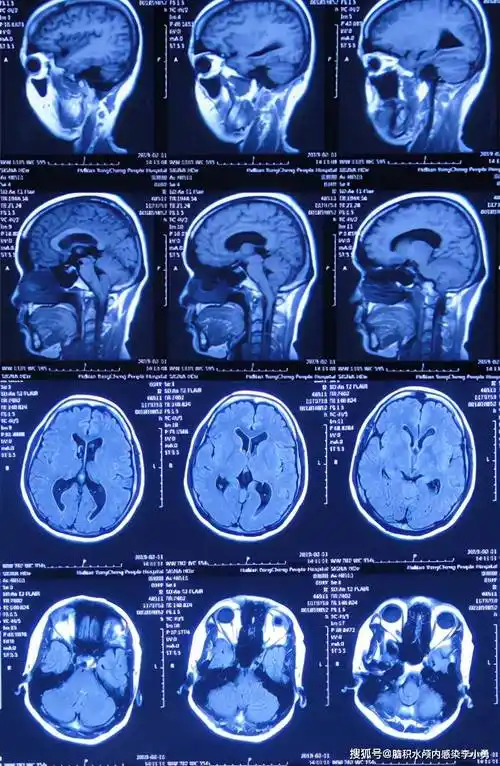

图-1:2019年2月10日头颅ct患者2019年2月初,因数次出现发作性黑蒙